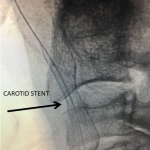

Figure 3.

Catheter angiography prior to angioplasty revealed critical stenosis (Figure 2). Angioplasty was therefore performed under local anesthesia with an embolic protection device deployed to catch any dislodged debris (Figure 3). After angioplasty, a stent was opened across the lesion to maintain long-term patency (Figure 4). Post-stent angiography showed smooth dilatation of the lesion. The patient’s aphasia continued to improve at his 6-week follow-up visit and duplex revealed no significant stenosis through the stent.